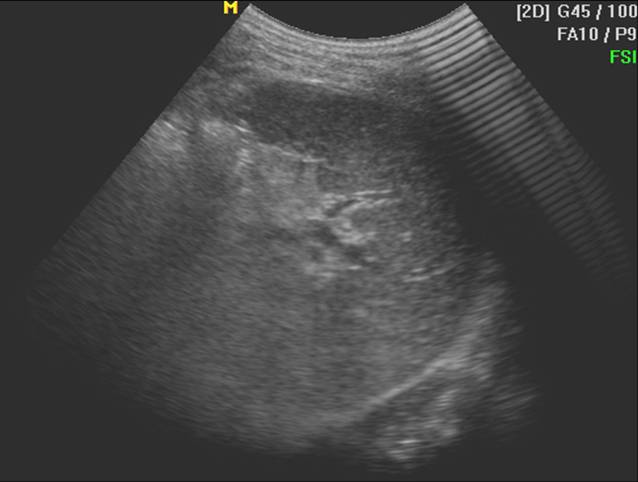

2 正常脾声像图